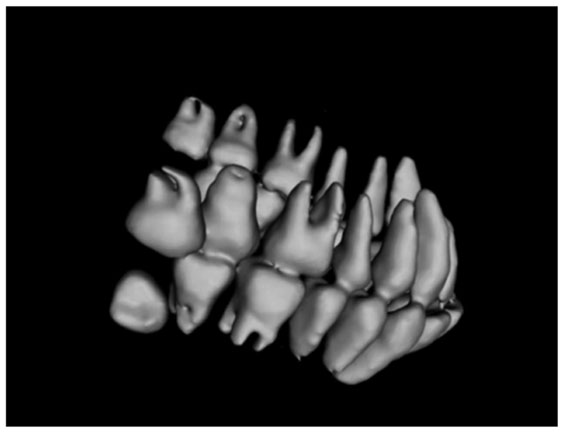

图 10. 采用本文算法对口腔CBCT数据进行三维重建的效果

Fig. 10. Reconstruction result of oral CBCT data using proposed algorithm

对比

上述实验采用的是一位阻生智齿患者的CBCT数据,通过重建可以从侧面清晰地看到病人的病情,明显看出该病人最里侧两颗牙齿的生长方向与正常牙齿完全不同,尤其是下方的阻生齿。实验结果表明本文方法在口腔医疗领域能够取得较好的应用效果。